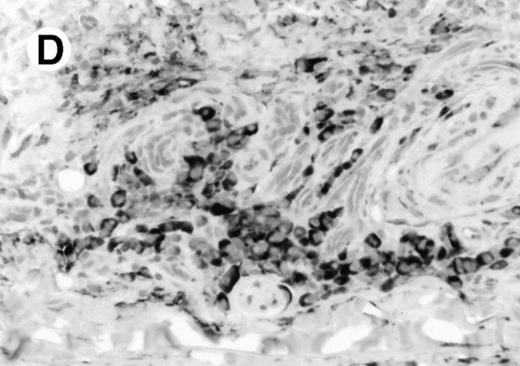

Both paraffin-embedded tissues and frozen sections (with or without heat antigen retrieval) were prepared for immunohistology as described in Materials and Methods. KPL1 stained numerous T cells in the T-zone (TZ) of a human tonsil (Fig 8A), but did not stain B cells in the mantle zone (M) or germinal center (GC) of the secondary follicles. Macrophages in the germinal center stained but follicular dendritic cells did not (Fig 8A). Just outside the germinal center, intense KPL1 staining of overlying plasma cells was observed. A high-power magnification (Fig 8B) shows this intense staining of plasma cells which surround the germinal centers. Subepithelial plasma cells also stained with KPL1 (data not shown), as did plasma cells around vessels in the skin (Fig 8C); these plasma cells costained with the plasma cell marker VS38 (Fig 8D). Thus, B cells located in germinal centers either lack the KPL1 epitope, or express it at levels which are not detected by these methods, whereas plasma cells in numerous sites express high levels. Similarly, four IL-6–dependent human myeloma cell lines expressed high levels of the KPL1 epitope (Diane Jelinek, personal communication, March 1997). Both cortical and medullary lymphocytes in the thymus stained with KPL1 (data not shown). Langerhans cells, bone marrow–derived antigen presenting cells which reside in the suprabasilar region of the epidermis, were also positive for KPL1 (Fig 8E). Langerhans cells in the tonsillar epithelium also stained with KPL1 (data not shown). Langerhans cells in soft tissue also stain with both KPL1 (Fig 8F) and CD1a (Fig 8G).

Expression of PSGL-1 in human tissues. (A) Paraffin tonsil stained with KPL1. The vast majority of the lymphocytes in the T-cell zone (TZ) show dark staining, while the B-lymphocytes in the mantle (M) and germinal center (GC) do not stain. (B) A high magnification of paraffin embedded tonsil stained with KPL1. Plasma cells adjacent to the overlying epithelium show dark membrane staining. The mantle B lymphocytes in the right lower corner do not stain. (C) Plasma cells near vessels in skin stain well with KPL1. (D) Costaining of the cells in (C) with VS38 confirms their identification as plasma cells.